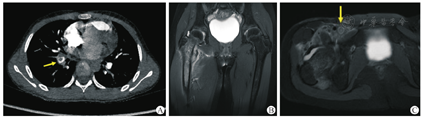

所有患儿都在外院完成四肢软组织超声和(或)血管超声检查并提示患侧肢体存在DVT,所有DVT位置均与急性骨髓炎感染灶位置相邻。在本院急诊行超声心动图检查均未见心脏结构异常及瓣膜赘生物;行血管超声检查并证实为DVT,其中20例病变累及下肢,1例累及上肢(表1)。所有患儿均行磁共振成像(magnetic resonance imaging,MRI)检查,MRI图像显示存在骨髓内异常信号、骨质破坏、关节积液、肌肉软组织水肿、关节积脓、骨膜下脓肿等表现(图1)。骨髓炎病变部位包括股骨14例,胫腓骨6例、肱骨1例;伴化脓性髋关节炎6例、膝关节炎1例。所有DVT位置均与MRI检查图像显示的急性骨髓炎感染灶位置相邻,如表1所示可见DVT和骨髓炎病灶位置。2例患儿因肺内病变行CT肺动脉造影(CT pulmonary arteriography,CTPA)检查发现右肺动脉栓塞(图1)。